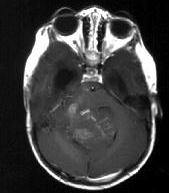

成年男性,头痛、头晕、恶心,病程二年余,结合影像图像选择最可能的诊断()A.脑膜瘤B.星形细胞瘤C.室管膜瘤D.胶质瘤E.畸胎瘤

问题 成年男性,头痛、头晕、恶心,病程二年余,结合影像图像选择最可能的诊断()

选项 A.脑膜瘤 B.星形细胞瘤 C.室管膜瘤 D.胶质瘤 E.畸胎瘤

答案 C